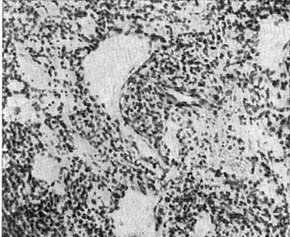

![]() Рис. 1. Злоякісна гемангиоэндотелиома. |

Гістологічно злоякісні гемангиоэндотелиомы характеризуються розростанням атипових ендотеліальних клітин, місцями з формуванням малодиференційованих судинних структур (рис. 1), подекуди солідного або альвеолярного будови. Клітини круглі, овальні або злегка витягнуті з великими, часто блідими або гиперхромными ядрами. У клітинах багато мітозів. Зустрічаються гігантські багатоядерні клітини. Малодиференційовані гемангиоэндотелиомы надзвичайно важкі для гістологічної діагностики і потребують спеціальних забарвлень, зокрема на аргирофильные волокна.